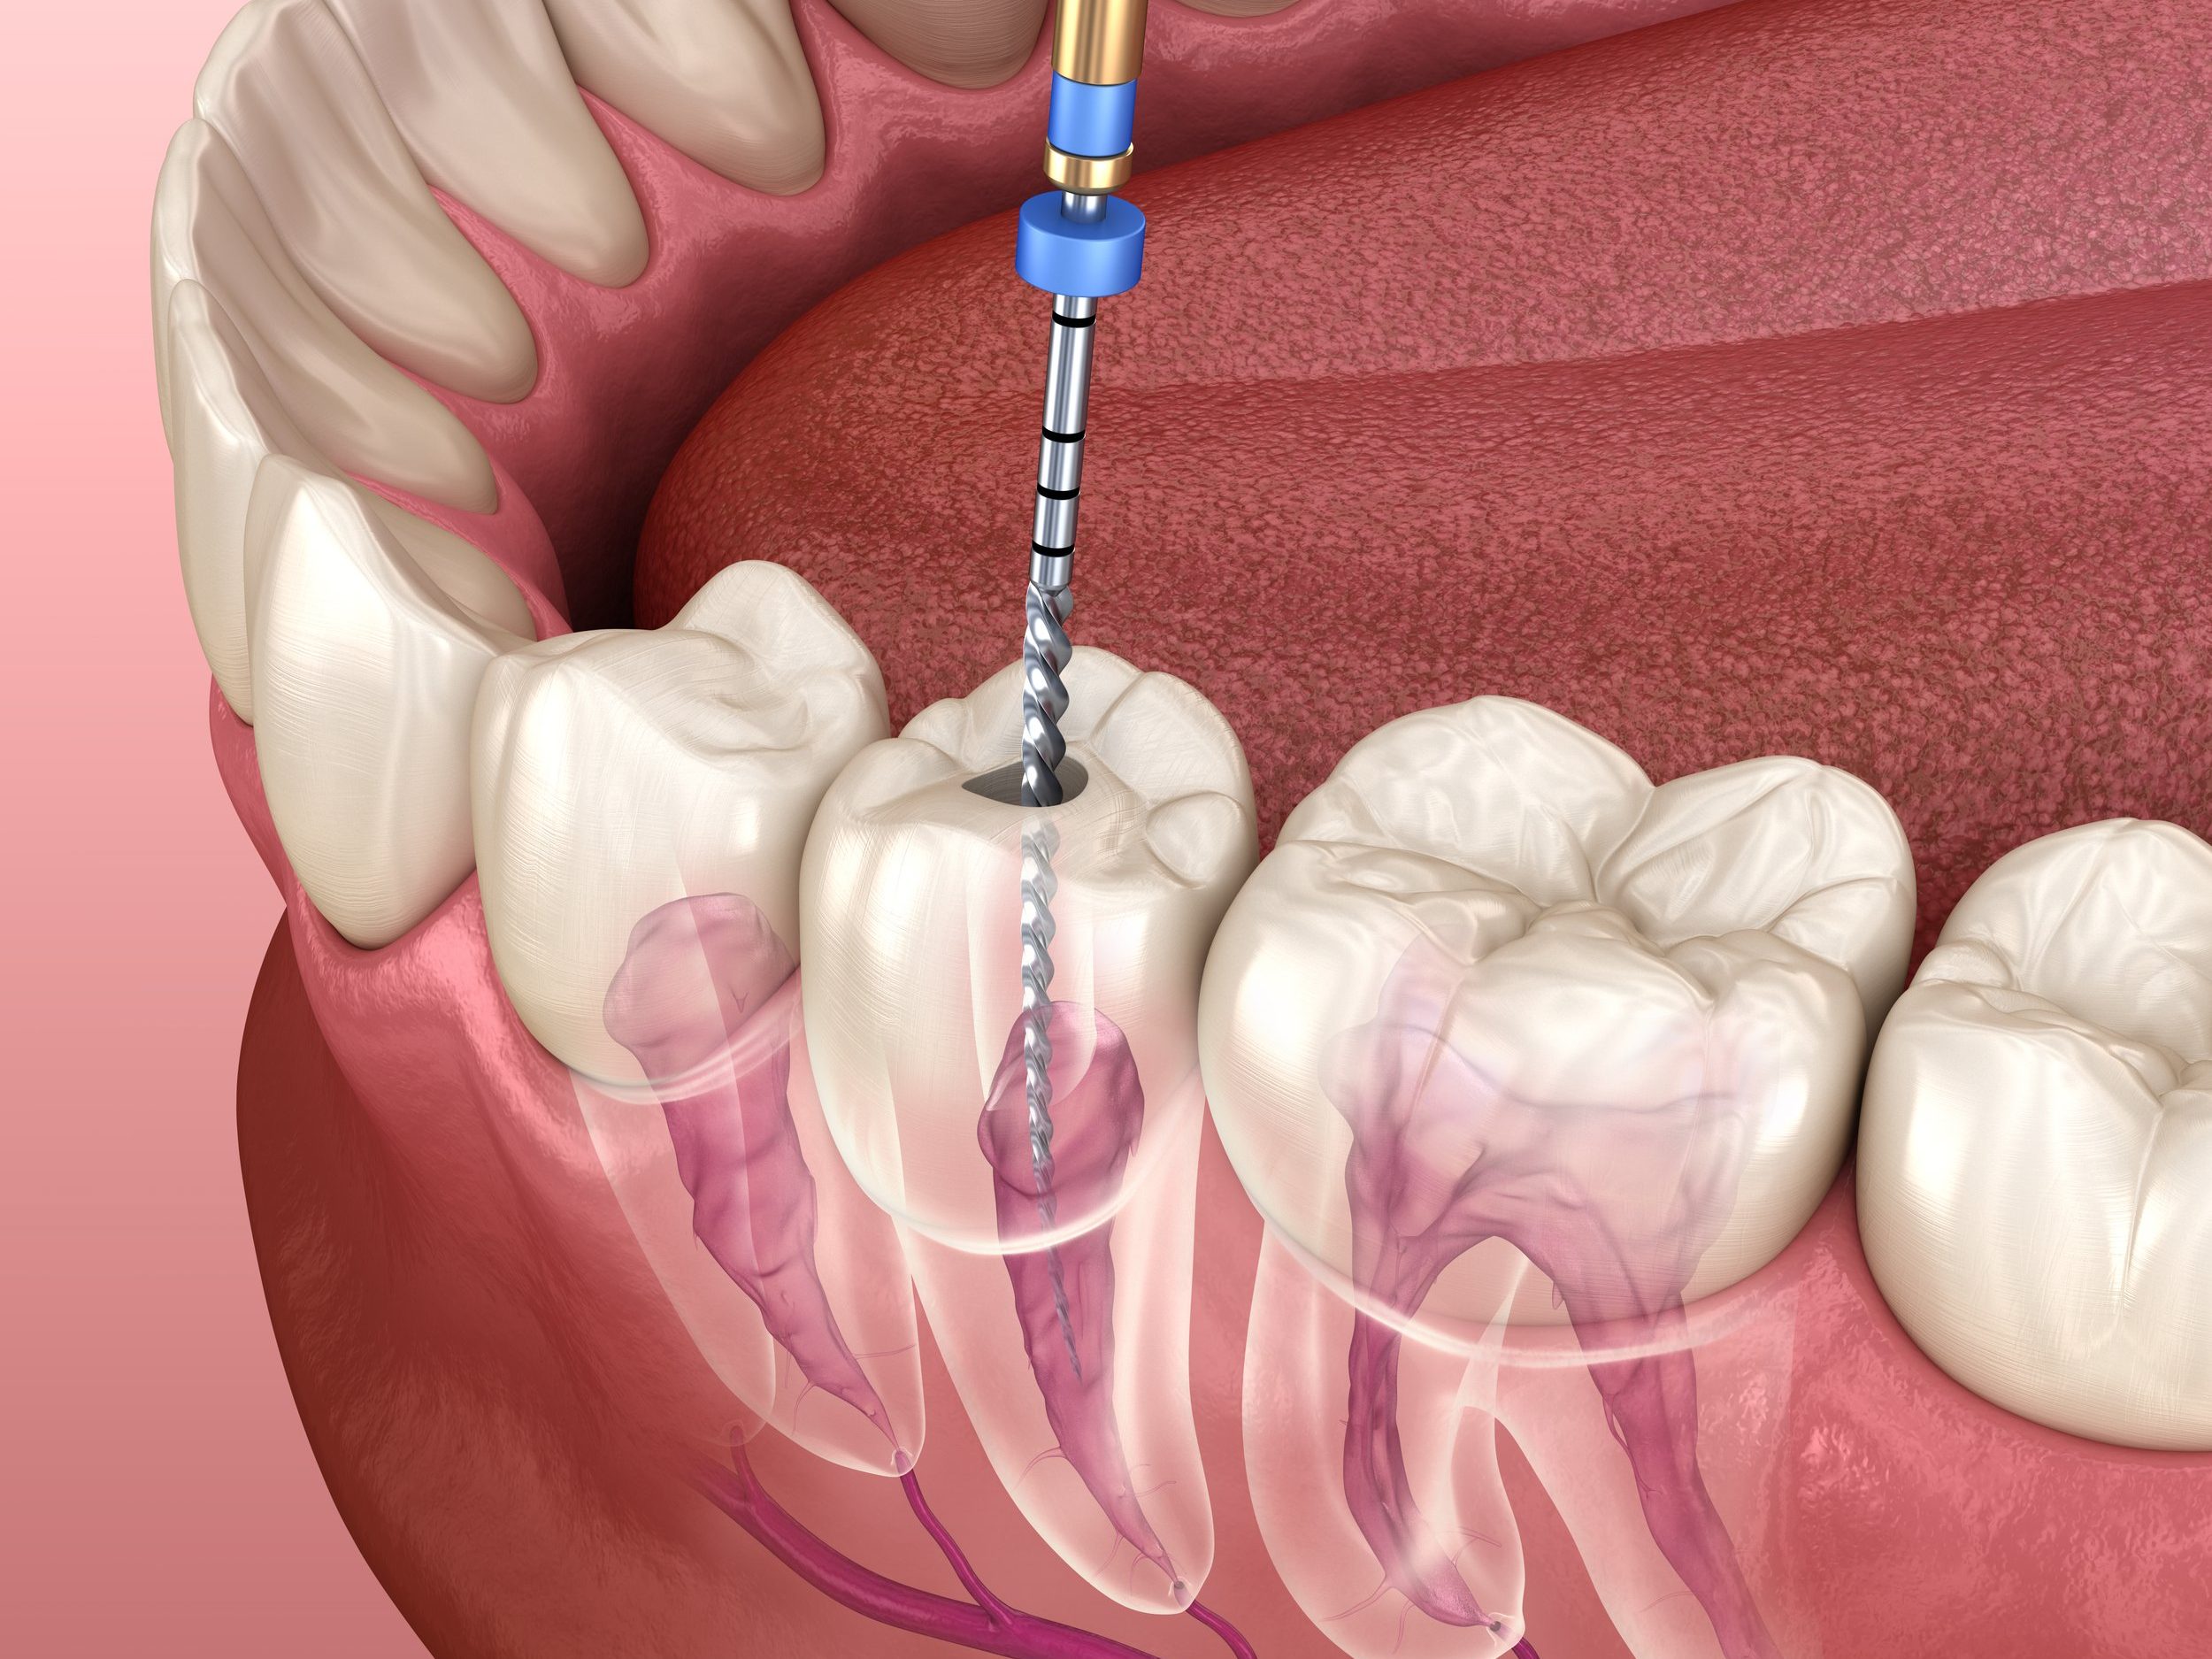

Endodontic Therapy

- Root Canal Treatment